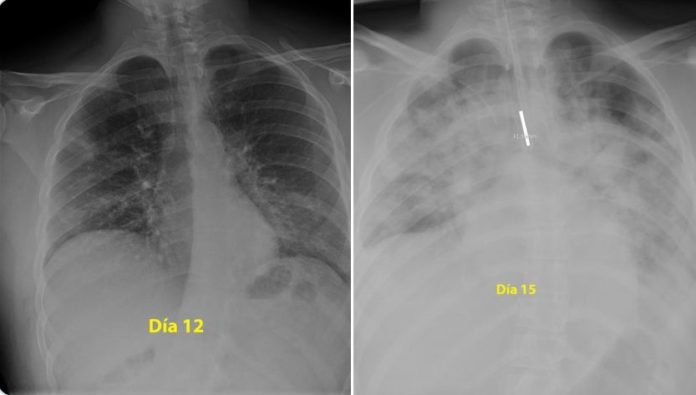

Un medic din Spania a publicat pe rețeaua de socializare Twitter două radiografii în care se vede cât de mult s-au degradat în numai 3 zile plămânii unui tânăr în vârstă de doar 28 de ani.

„Pentru toți cei care se cred nemuritori și se gândesc să iasă în parc în ciuda ordinului de carantină la domiciliu, iată radiografiile unui tânăr de 28 de ani cu coronavirus intubat la terapie intensivă în spitalul la care lucrez. Indiciu: plămânii sunt partea neagră, partea albă este pneumonia”, a scris medicul.

Pneumonia este una dintre complicațiile pe care le poate produce virusul SARS-CoV-2.